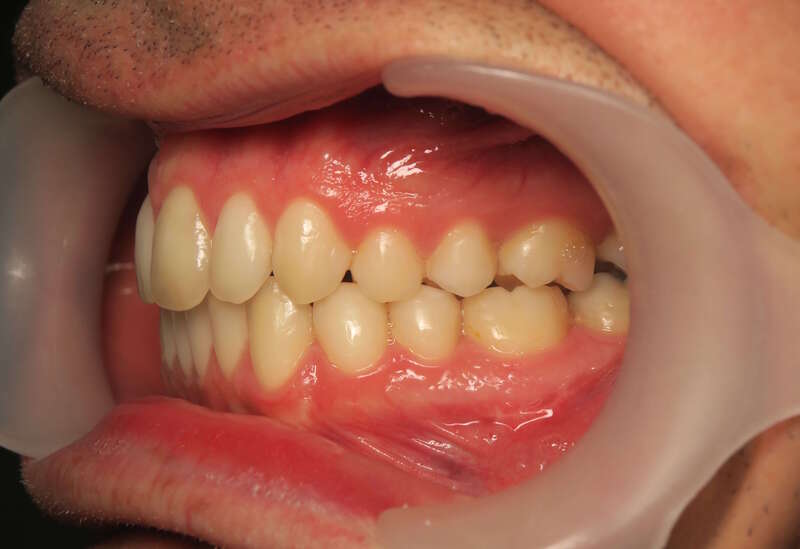

Cas n°9 traité par multi-attaches - adolescent

Ce cas d'adolescent illustre une stratégie de développement d'arcade réussie. Le patient présentait un encombrement massif et des inversions d'articulé rendant l'occlusion instable.

Le traitement a été réalisé avec des multibagues autoligaturantes, choisies pour leur capacité à générer des forces légères et continues, idéales pour l'expansion transversale. Cette approche a permis de corriger l'encombrement et les inversions d'articulé sans extractions dentaires, en remodelant simplement la forme des arcades.

Résultats clés :

• Transformation d'arcade : Passage d'une arcade étroite et encombrée à une arcade large et fonctionnelle.

• Occlusion optimale : Rétablissement d'un engrènement sain, protégeant les dents contre les usures anormales.

• Esthétique naturelle : Le sourire est élargi, harmonieux et parfaitement intégré au profil du patient.

C'est une démonstration de l'efficacité biologique de l'orthodontie moderne, qui privilégie la conservation dentaire et le respect des structures osseuses.